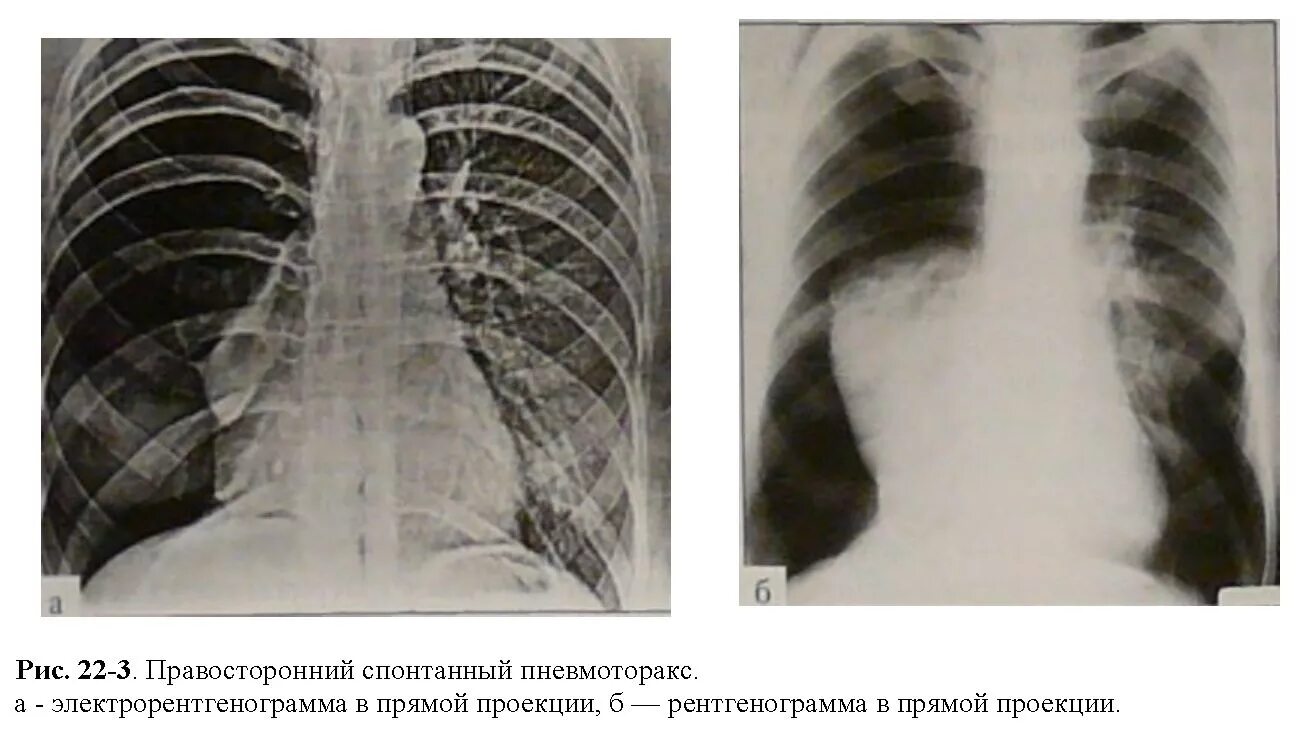

Коллабированное легкое при пневмотораксе